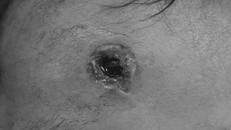

Viên đạn găm vào trán bên phải của cháu bé

Nghịch súng bắn chim, bé trai 33 tháng tuổi bị đạn bi bắn xuyên sọ não

(Ngày Nay) - Trong lúc các chị em lấy súng bắn chim tự chế của cậu chơi đùa, nòng súng bất ngờ bóp cò khiến viên đạn bay thẳng vào đầu bé trai.